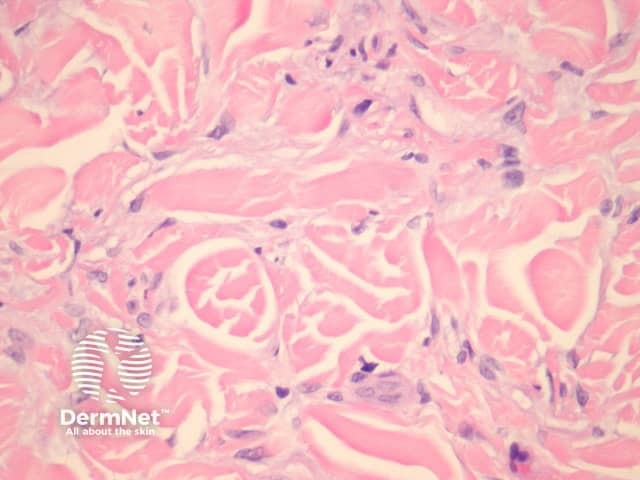

Lipidised dermatofibroma is also known as ‘ankle type’ dermatofibroma due to a predilection for the lower leg. Histologically, foamy histiocytes predominate with marked hyalinization of collagen resembling amyloid (figure 12).

Figure 12